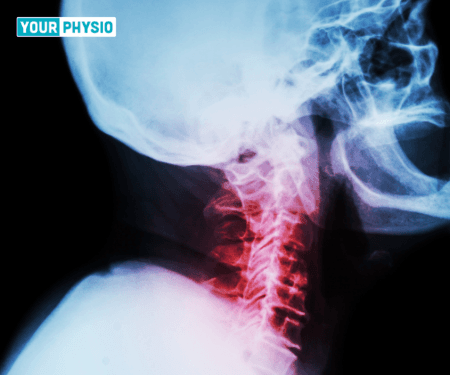

X-ray of the cervical spine is the commonest examination of decision. An X-ray gives a picture of the alignment of vertebrae or bone.

Plain radiographs of the cervical spine might show a deficiency of typical cervical lordosis. Lordosis can cause the muscles of the back to contract and some muscles to be in the lengthened position for a prolonged time. This can further lead to muscle spasms.

Most patients don't require further examination and the analysis is made on clinical grounds alone. However, an X-ray, CT, MRI, and EMG can be utilised to affirm a diagnosis.